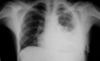

¿Qué es esto?

Perforación de víscera hueca